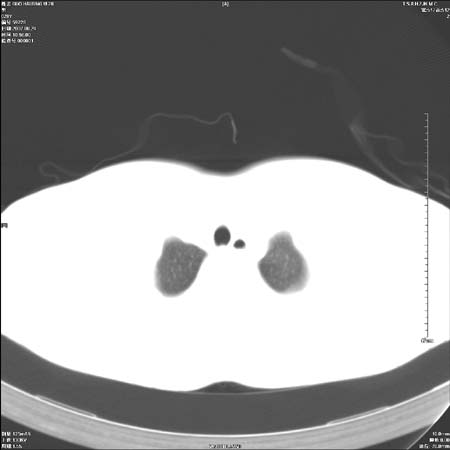

左肺门区软组织肿块,左肺上叶支气管开口消失,纵隔内见肿大淋巴结,考虑左中心型肺部,可以做纤支镜取病理确认.

首先这个病例应该加薄层面扫描-可以很好显示支气管与肿块的情况。

左肺肺门区肿块影,分叶明显,左肺上叶支气管开口受压,纵隔内见肿大淋巴结,考虑左中心型肺癌。

左侧肺门区见一块状病灶可见分叶,纵隔内及左肺门见肿大淋巴结,应该是周围型肺癌而不是中心型肺癌,原因有以下2点,1未见阻塞肺气肿和阻塞性炎症,这么大肿块如果是中心型肺癌就是未分化型或小细胞型肺癌不出现阻塞性肺不张也应该有阻塞炎症或阻塞性肺气肿,2如果是中心型肺癌临床出现最早的症状是咳嗽(此时可无任何异常影象),而此人这么大肿块只有背部隐痛是体检才发现无法解释.

左肺门区分叶状软组织肿块,纵隔内有肿大淋巴结,诊断肺癌应该问题不大。

直接下肺癌诊断还太早,病灶较大,估计5cm以上,但阻塞性改变及对临近纵隔及支气管侵犯不明显,密度较均匀,弓旁见一单个淋巴结,需要排除炎症性肿块及腺瘤,平滑肌瘤等。